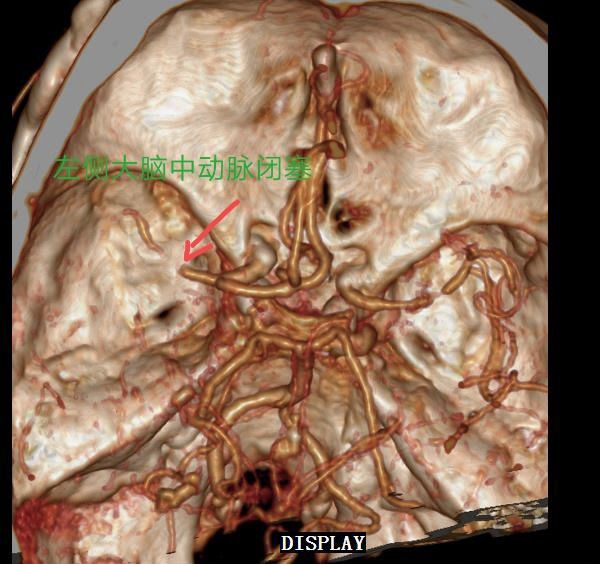

急诊头颅CTA:左侧大脑中动脉闭塞,右侧大脑中动脉重度狭窄或闭塞。